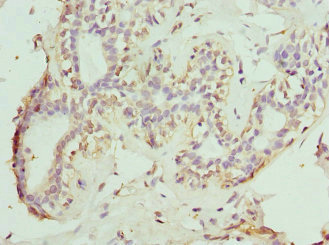

Immunohistochemistry of paraffin-embedded human breast cancer using CSB-PA138304ESR2HU at dilution of 1:100